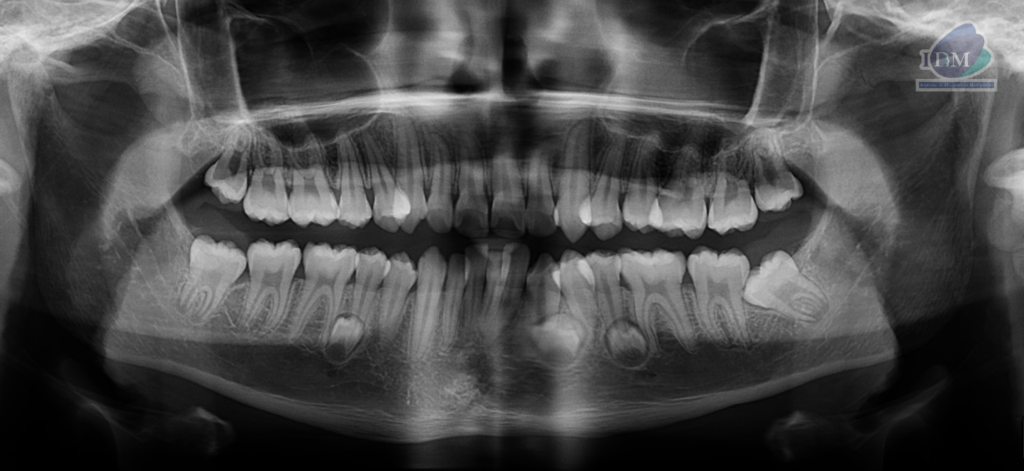

Radiografia Panorámica

A la evaluación de la radiografía panorámica se evidencia tres folículos supernumerarios en cuerpo mandibular de ambos lados.